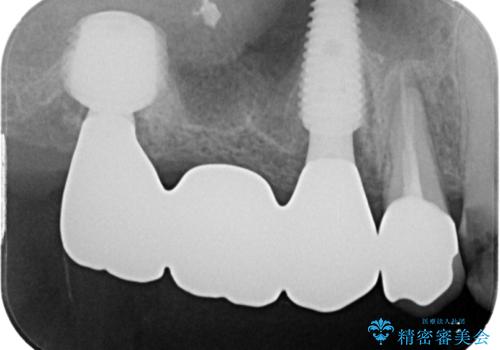

- 土台の歯が割れてしまって、歯がグラグラしているとのことで来院された患者様です。

いずれの歯も抜歯が必要な状態であり、抜歯即時埋入によるインプラント治療を行うこととしました。

右上奥歯は骨欠損の範囲が広いため、抜歯即時埋入は可能であっても、即日で仮歯を装着する即時荷重は難しいと判断されたため、手前の歯まで仮歯を装着することとしました。

術後にインプラントの安定値を測定し、十分な値が達成された後、速やかにセラミッククラウンにて補綴治療を行うこととしました。